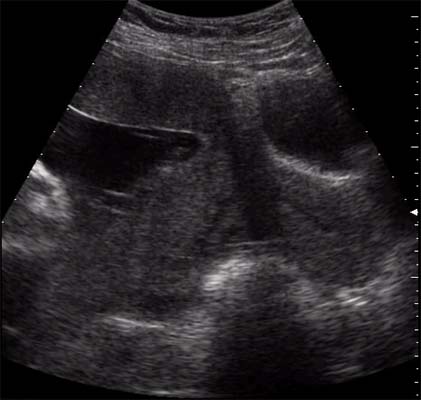

Clivage par un hématome de l’espace virtuelle entre la plaque basale et la paroi utérine.

Massif, il décolle presque totalement le placenta et entraîne une symptomatologie maternelle bruyante et la mort fœtale. L’échographie montre alors un placenta flottant sur un caillot ou une vaste lacune anéchogène.

De volume plus réduit (n’excédant pas plus du quart de la surface placentaire), il évolue sous forme d’une MAP hémorragique ou sous forme d’une souffrance fœtale.

Hématome organisé :

- Echogénicité voisine de celle du placenta mais souvent moins homogène

- Siège au niveau basal

- Le soulèvement de la plaque basale est évident lorsqu’elle est calcifiée

- Parfois se réduit à un simple épaississement localisé du placenta ?